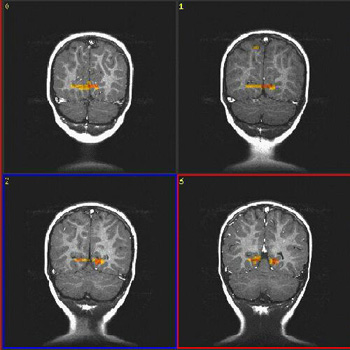

Case 2

| Patient | 18 month-old-boy with mild cerebral palsy | ||||||

| Paradigm | ON: Presentation of mother's voice, pre-recorded, using familiar words and sounds OFF: Nothing. Patient sedated with propofol | ||||||

| Statistics |

| ||||||

| Activation | Activation of auditory areas are well depicted. There is bithalamic activation. The strong activation of the right parasagital frontal lobe is not well understood. |